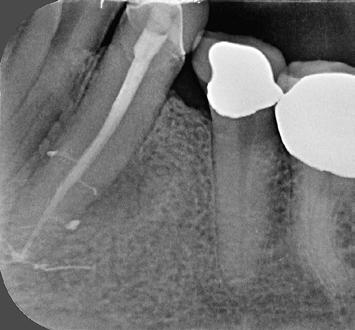

10. ábra: A periapikális felvételen egyértelműen megmutatkozik a 46-os és 47-es fogak között kialakult csontos defektus, valamint a gyökereket fedő parodontális rostok károsodása. – 11. ábra: A disztális gyökér amputációját követően a csonthiány kiterjedése látszólag tovább növekedett. – 12. ábra: A 22 évvel később készített kontrollfelvételen jól megfigyelhető a csontos defektus telődése, valamint új kortikális csontállomány kialakulása.

Gyökéramputációt főként a furkáció érintett nagyőrlő fogak ellátása során szoktunk alkalmazni. Derks és mtsai. vizsgálatában a gyökéramputált nagyőrlő fogak közel 80%-a 20 évvel a beavatkozás elvégzését követően is megtartott volt. 1998 októberében egy 39 éves férfi páciens a jobb alsó kvadránsban jelentkező ínyérzékenység miatt kereste fel rendelőnket. A klinikai vizsgálat során jobb alsó első és második nagyőrlő fog között (46–47) nagy kiterjedésű csontveszteséget észleltünk. Ettől eltekintve a teljes fogazat parodontális státusza megfelelőnek bizonyult. A jobb alsó kvadránsban végzett szenzibilitás vizsgálat során arra az eredménye jutottunk, hogy a 46-os fog vélelmezhetően elhalt (10. ábra).

A páciens beleegyezését követően a 46-os fog disztális gyökere, a disztális gyökér felett lévő koronális rész megőrzése mellett rezekcióra került (11. ábra). A rezekciót követően a referáló orvos a 46. és 47. fogak koronáját Ribbond szalag és kompozit segítségével egymáshoz rögzítette. A sebészi beavatkozást követően 22 évvel készült kontrollfelvételen a lézió csontos telődése, kortikális csontállomány kialakulása, valamint a furkáció körüli csontos regeneráció volt megfigyelhető (12. ábra) A károsodott fogak megtartására szolgáló lehetőségek fejlődésének, valamint az implantátumok behelyezésével kapcsolatos rizikófaktorok jobb megértésének köszönhetően ma már más szemmel vizsgáljuk a fogak eltávolításának szükségességét. A kérdéses prognózissal vagy a kis protetikai értékkel rendelkező fogak eltávolítása előtt mindig érdemes felmérni az ezzel elérhető lehetséges előnyök nagyságát. A kemény- és lágyszöveti pótlás lehetőségeinek fejlődésével, a PRF elérhetőségével, a minimálinvazív sebészeti módszerek és az operációs mikroszkópok elterjedésével, valamint a varróanyagok és varrat technikák egyre kifinomultabbá válásával ma már alaposan el kell gondolkodnunk az előtt, hogy egy fogat egy implantátum behelyezése érdekében eltávolítsunk. Mára sokkal kedvezőbb prognózist és sokkal nagyobb sikerességet tudunk elérni a korábban menthetetlennek gondolt fogak kezelése során.